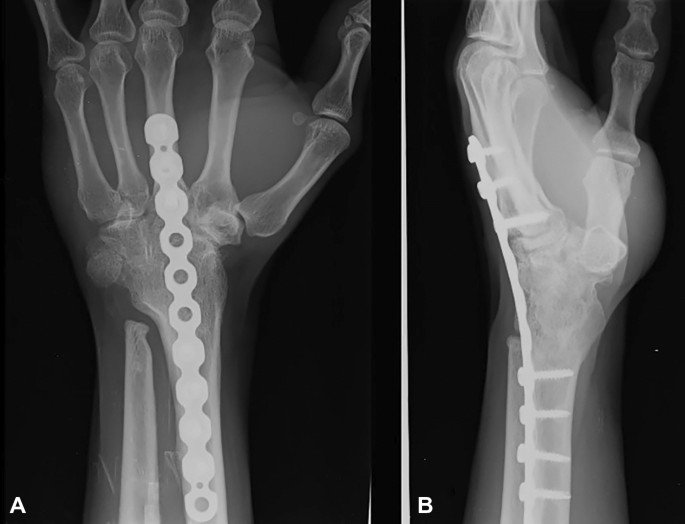

Arthrodesis of wrist joint

Arthrodesis of wrist

It may be defined as surgical fusion of the radiocarpal joint.